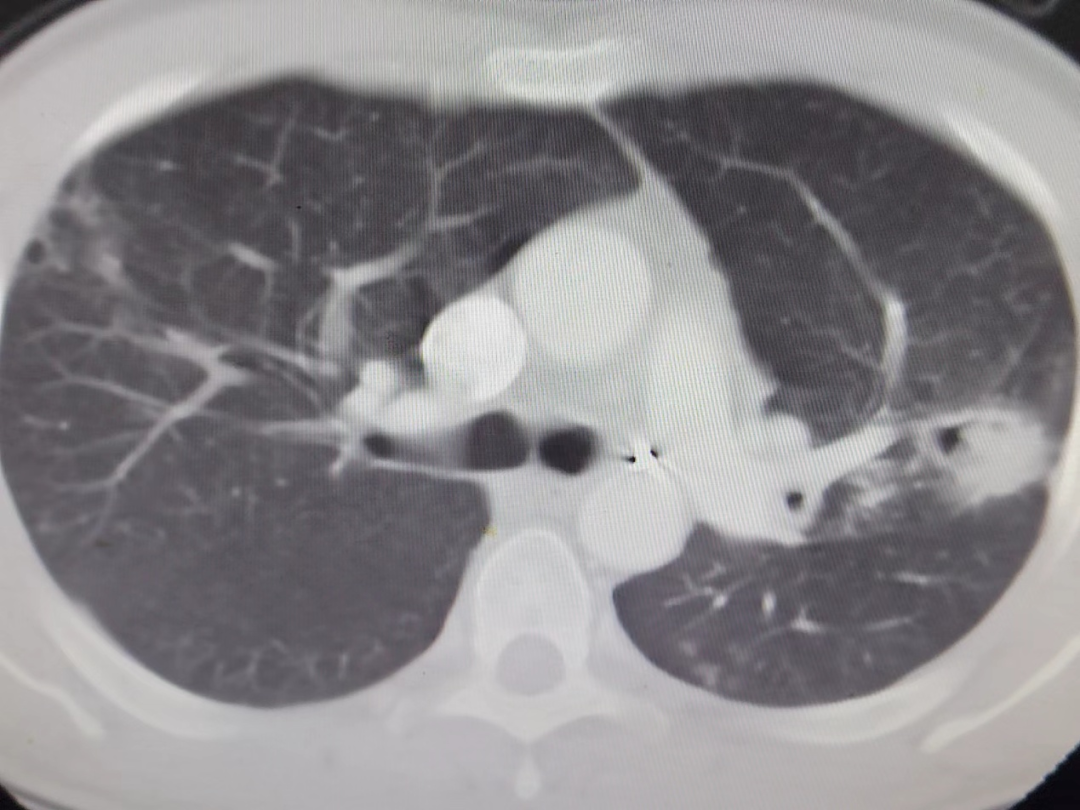

术前左肺空洞型病灶

术前胸部CT,见空洞内曲菌球